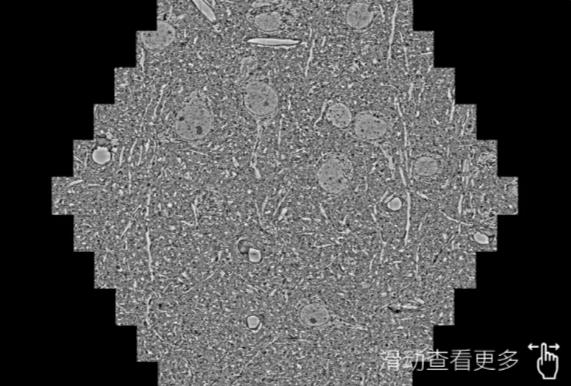

鼠脑切片。左图使用芜湖蔡司芜湖扫描电镜MultiSEM706对165μmx143pm面积区域成像,耗时仅需1.5秒。右图为鼠脑切片中30μm区域放大效果。样品由芝加哥大学B.Kasthuri提供。

使用蔡司高速芜湖扫描电镜MultiSEM对1mm²人脑皮层组织进行高分辨成像,并对其中的各种细胞结构进行三维重构分析。左图展示了2x3mm²组织平面中锥体神经元的三维重构效果。右图显示了局部体积神经元三维重构。图像由哈佛大学chtman实验室提供,渲染图由D. Berger 制作。